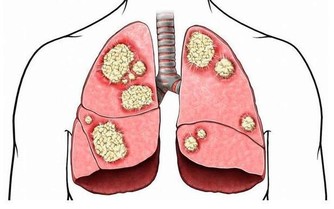

三、感冒怎麼喝:

要喝比平時更多的水,每到感冒的時候,就會聽到醫生嘮叨:「多喝水呀!」這句醫囑對於感冒病人是最好的處方。因為當人感冒發燒的時候,人體出於自我保護機能的反應而自身降溫,這時就會有出汗、呼吸急促、皮膚蒸發的水分增多等代謝加快的表現,多多喝水不僅促使汗出和排尿,而且有利於體溫的調節,促使體內細菌病毒迅速排泄掉。